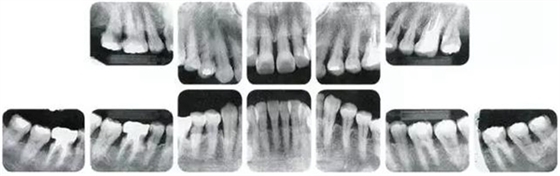

●參考病例② 25歲女性

25歲女性。菌斑控制狀態(tài)不好。齦溝除磨牙處外全在3mm以下,X光照片上左上、右下、左下的第一磨牙上有垂直性骨吸收。這個(gè)病例是參考病例①10年前的狀態(tài),是典型的侵襲性牙周炎局部型。